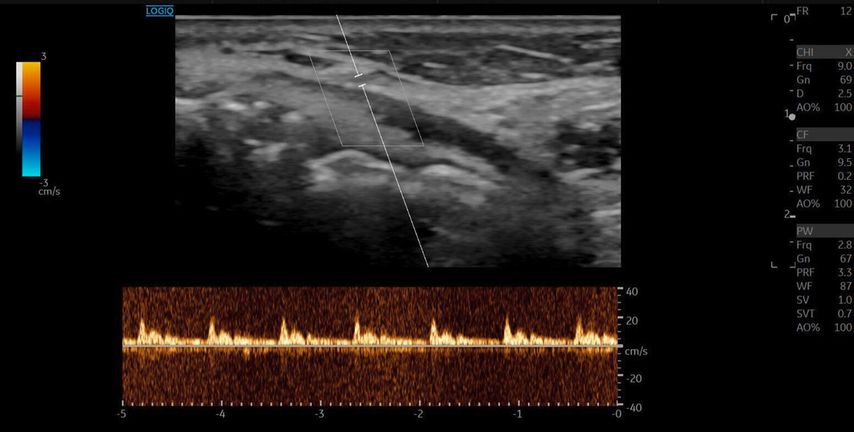

Die A. facialis imponierte beim Austritt im Bereich des Musculus masseter (oberhalb der Kieferlinie) vasospastisch mit einem maximalen Durchmesser von 1mm. Die abgeleitete systolische Spitzengeschwindigkeit betrug trotz der bestehenden Ischämie 20cm/s, ohne enddiastolische Komponente, was auf eine weitere periphere Vasokonstriktion hindeutete (Abb. 2 und 3).

Die Duplexsonografie ergab folgende Befunde (Abb. 5 und Abb. 6):

Der Durchmesser der A. angularis und A. facialis hatte sich nahezu verdoppelt.

Die systolische Spitzengeschwindigkeit (PSV) stieg von 20cm/s auf über 100cm/s.

Die enddiastolische Geschwindigkeit (EDV) betrug nun 20cm/s, was auf eine periphere Vasodilatation und eine Wiederherstellung der Makrozirkulation hindeutete (Abb. 7).